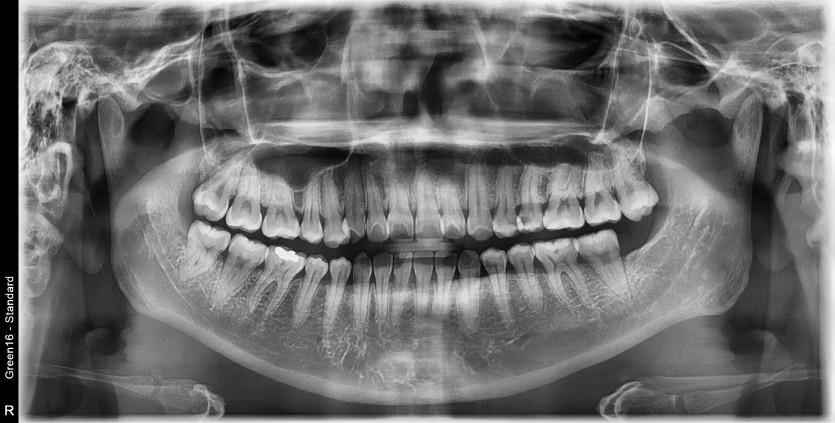

#18,48 사랑니 발치

구강 외과 전문의가 당일 발치했습니다.